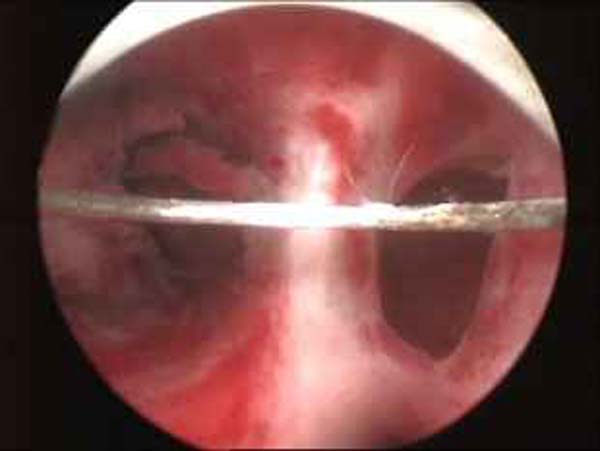

- Hysteroscopy Video clips

- Hysteroscopy Photos

Hysteroscopy Pictures | Dr N Layyous